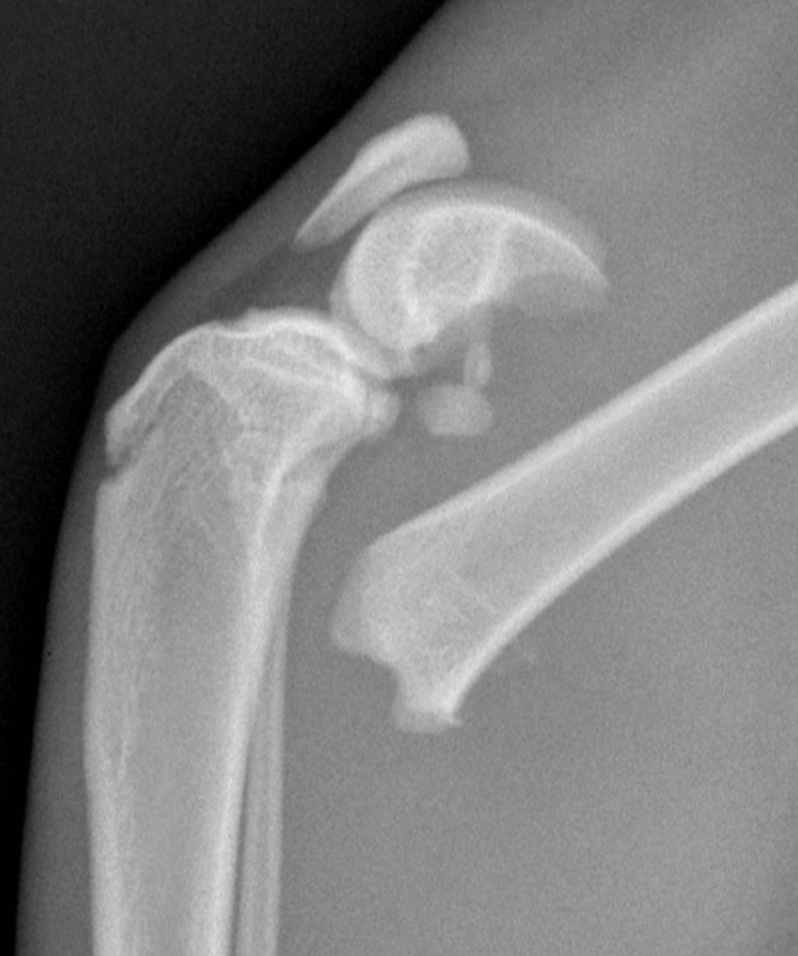

Fracture Salter Harris Type I du fémur distal chez Olaf

Fracture Salter Harris Type I du fémur distal chez Olaf (profil et face)